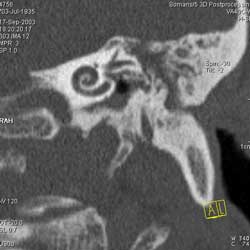

Рис. 10. Принципы КТ высокого разрешения (КТВР) на примере исследования

пирамиды височной кости. Применены тонкие срезы (0.5 мм) и "острый" алгоритм

реконструкции (кернель 90). (Слева) отчетливо видны элементы внутреннего

уха - улитка, полукружные канальцы. (В центре) показана проекция продольного

сечения височно-нижнечелюстного сустава. (Справа) - холестеатома.